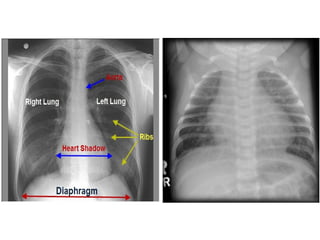

NORMAL HEART

VSD - HYPERTROPHY

NORMAL HEART VSD -HYPERTROPHY